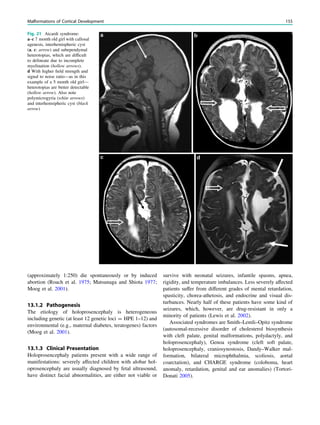

Delalande O, Bulteau C, Dellatolas G et al (2007) Vertical parasagittal

hemispherotomy: surgical procedures and clinical long-term out-

comes in a population of 83 children. Neurosurgery 60(2 Suppl

1):ONS19–ONS32

Delalande O, Pinard JM, Basdevant C et al (1992) Hemispherotomy: a

new procedure fro central disconnection. Epilepsia 33(Suppl3):